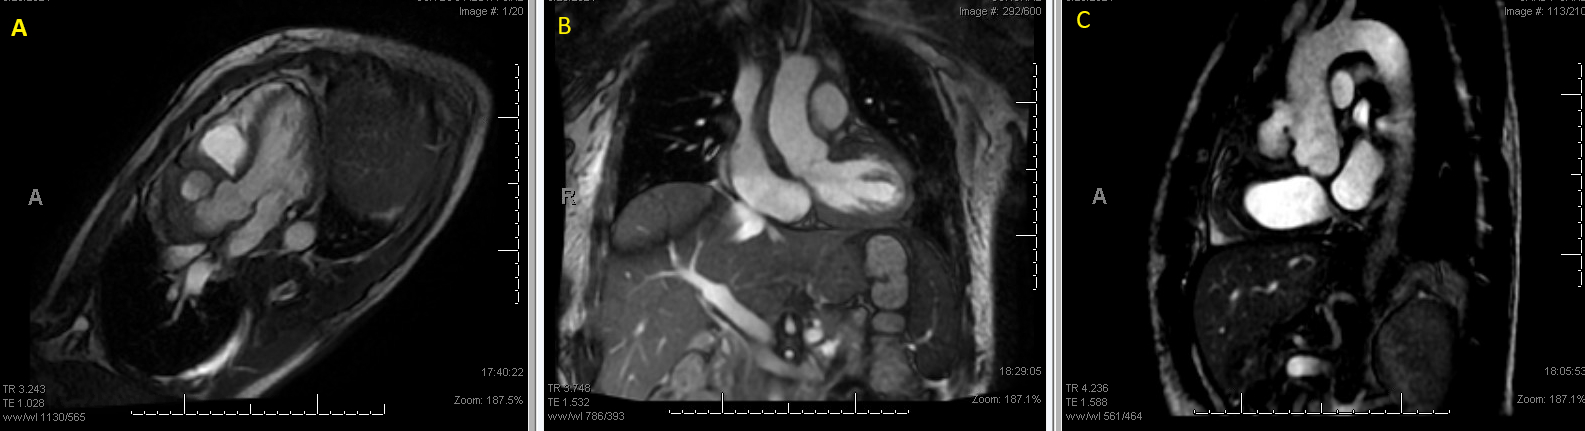

Abstract Body (Do not enter title and authors here): Description of Case: A 57 y.o. male with a hx of prior MSSA bactermia and RCA aneurysm presented for intermittent fevers. His exam showed a harsh systolic murmur at the pulmonic post. ESR and CRP were elevated at 78 mm/hr and 17.1 mg/dL, respectively. WBC of 32.1 x 10e3/uL and a HGB of 8.8 g/dL. Blood cultures were positive for MSSA. Imaging with a CTA Chest, TTE, TEE, and cardiac MRI showed a multilobular 5 x 2.5 x 5.3 cm PSA originating from the proximal ascending aorta.

It is worth noting is the compression of the pseudoaneurysm on the pulmonary artery. This is a very rare complication of ascending aortic pathology. In our patient, pulmonary artery compression was noted on his initial imaging and persistent throughout. However, right heart failure did not develop until his immediate post-operative course, and it’s possible that the necessary shifting of his pseudoaneurysm within his operation contributed to worsening compression on his pulmonary artery and subsequent mortality.